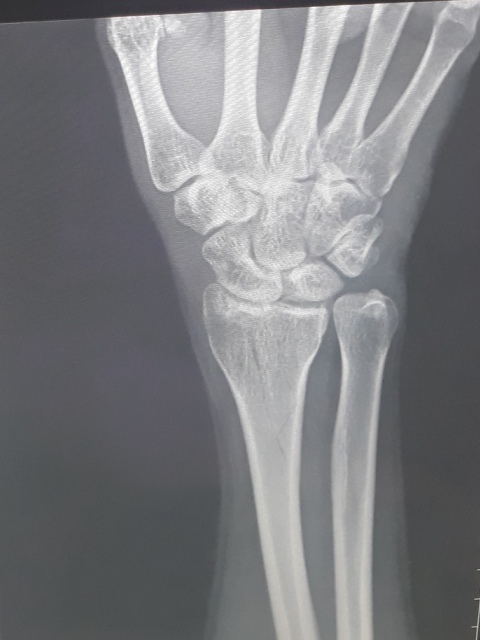

右手X光↓

進入門診前,我自認為手比腳恢復還快,因為比起一開始,手指比較能出力了,手腕可轉動的範圍也變大了。腳因一直用副木石膏固定住,不能動,所以也不知恢復多少。進入門診後,黃醫師說斷裂的骨頭都沒移位。手沒什麼進展(骨頭不會長那麼快),腳的部份下回再來復診時,可能會恢復的較快了。

手沒什麼進展這件事,讓我比較吃驚,詢問黃醫師,手如果也改用副木,會不會比較好,黃醫師說,他個人是認為沒什麼差。他看著X光片照出來的結果,說開刀或不開刀他覺得都差不多。

或許今天是228放假日,來醫院看病的人蠻多的,我們等了一段時間才被叫到。進到診間後,黃醫師調出X光資料,發現橈骨已癒合很多了,讓我感到很吃驚,兩個星期前還是很明顯的骨裂,現在已經看不太到了(小純說,一定是峰王膠原飲發揮了功效,這兩週內,膠原蛋白喝了八罐了)。黃醫師說,我的手腕護具可以拿掉了,我拿起護具後,黃醫師拉了我的手腕做一些轉動的動作,還是有些痛,黃醫師叫我要多做熱敷,手可以開始做復健了,也可以讓手開始做一些事情,但避免提重物,兩個星期後再回診看角度。

之後,我去照了X光,因為一個月前照X光,感覺已經快好了,我以為今天去照,骨頭應已癒合的差不多了。結果照出來之後,竟然還能看的到裂痕,讓我大吃一驚。唉....可能要等一陣子才會好。

今日所拍攝的X光照↓